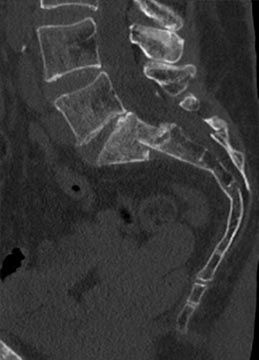

73 year old woman with osteoporosis who fell and fractured her pelvis. She was unable to walk and developed lumbopelvic dissociation (seperation of the spine from the pelvis and lower half of the body) from an unstable sacral fracture and displacement.

Lumbopelvic fixation with prophylactic cement augmentation and patient was immediately able to walk again.